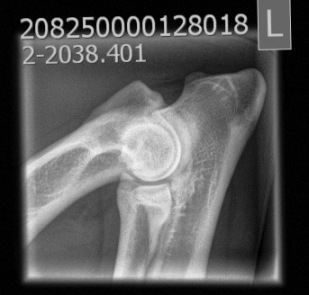

AD: 0/0